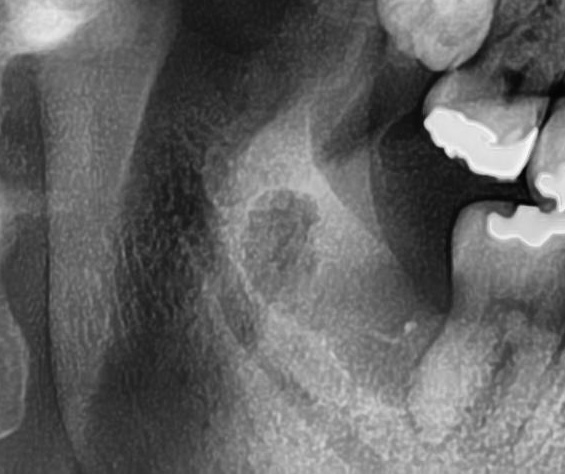

次にパノラマ写真を撮影してみると、右下の親知らずは、手前の歯の根っこを押すように横向きに生えているのが確認できました。